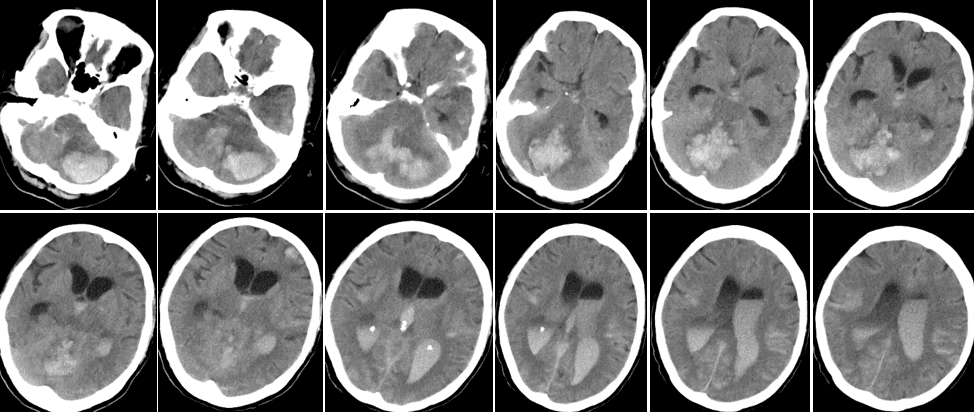

头CT(2023-11-6)见双侧小脑团片状高密度影,相应小脑及脑干组织密度减低。双侧侧脑室、第三脑室、第四脑室见较多高密度影。脑池、脑沟内见线杨高密度影。双侧额叶、右侧顶叶皮层下见多发结节样高密度影,大者直径约1.3cm,边缘模糊。影像结论颅内多发转移瘤、瘤卒中可能,伴脑室积血、蛛网膜下腔出血。